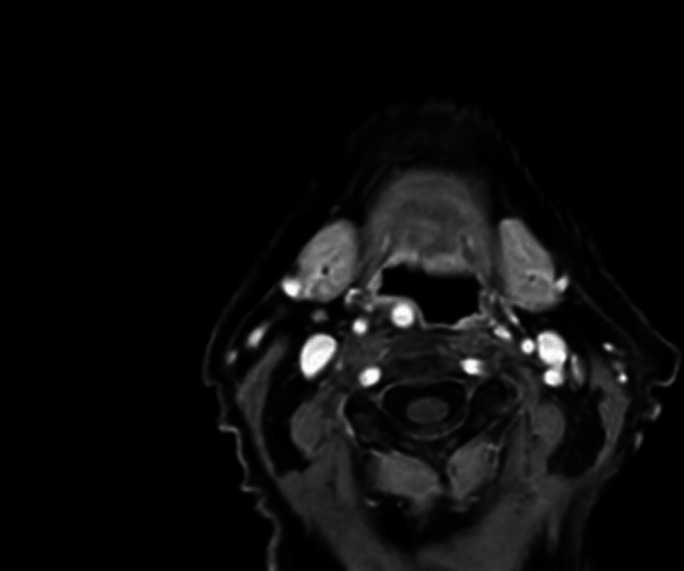

Purpose: We present a case of dysphagia caused by an aberrant internal carotid artery (ICA). By reporting this rare occurrence, we hope to highlight the anomaly as a differential in cases of persistent, progressive dysphagia.

Results: Even though the symptomatic mass effect of the ICA warranted the option of surgical intervention, due to a patient-centered approach with an emphasis on personal preference, the patient was instead referred for specialized ergotherapy.